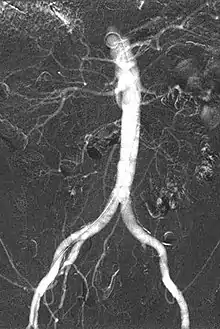

Carbon dioxide angiography

Carbon dioxide angiography is a diagnostic radiographic technique in which a carbon dioxide (CO2) based contrast medium is used - unlike traditional angiography where the contrast medium normally used is iodine based – to see and study the body vessels.[1] Since CO2 is a non-radio-opaque contrast medium, angiographic procedures need to be performed in digital subtraction angiography (DSA).

Carbon dioxide is a negative contrast medium and it has a low radiopacity (while iodinated contrast media are defined as positive contrast media due to their high radiopacity). Contrast is caused by the different X-ray absorption coefficients between the tissue and the contrast agent. In the vascular imaging results produced using CO2, vessels look brighter rather than the surrounding tissues, because the contrast medium absorbs less X-ray radiations rather an iodine-based contrast medium, where the vessel are displayed in black.

The CO2 does not mix with blood. At atmospheric pressure CO2 is in gaseous form and, when it comes out from the catheter, it forms a train of bubbles which displaces blood, causing a transient ischemia, in relation to the bloodstream (systolic pressure). When added together by DSA “stacking” software,[5] the result is a composite diagnostic image of the frames.